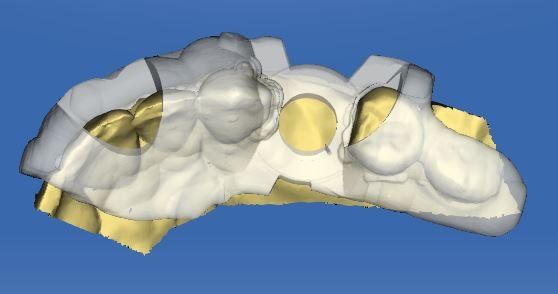

From simple x-rays and cbct datasets, to implant guides and placements.